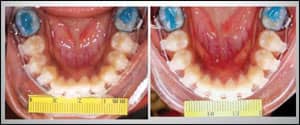

The BioMers archwire was introduced into the orthodontic market at the 2008 AAO Annual Session. This release followed successful clinical trials at two American postgraduate orthodontic programs. At the School of Orthodontics at Jacksonville University, 46 patients underwent a pilot study using a 0.018-inch BioMers wire for up to a 4-month period. The focus of the study was the initial phase of therapy dealing with leveling, aligning, and rotation. Specific inclusion criteria were used, and the entire protocol was approved by the University’s Institutional Review Board. Patients for whom wire deflections with angulations of greater than 60º were necessary were excluded from the study. The results of a pilot study comparing 0.018 BioMers wire to a 0.014 nickel titanium wire over the initial phase showed no differences in the correction of incisor irregularity between the two groups.

![]() |

| Figure 1: Plastic tubing has been placed on the posterior sections. |